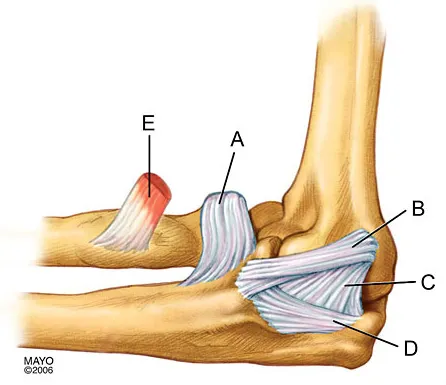

In Figure 2, which of the following structures is the primary stabilizer in preventing valgus instability of the elbow?

The anterior bundle of the medial collateral ligament is the prime stabilizer of the medial aspect of the elbow and is indicated by "B" in the figure. When intact, this anterior bundle of the medial collateral ligament is a restraint to valgus instability of the elbow. The posterior bundle is regarded as a secondary stabilizer of the medial elbow (C). The transverse bundle (D), annular ligament (A), and biceps tendon (E) do not play a role in valgus stability of the elbow. Jobe F, Elattrache N: Diagnosis and treatment of ulnar collateral ligament injuries in athletes, in Morrey B (ed): The Elbow and Its Disorders. Philadelphia, PA, WB Saunders, 1993, p 566.